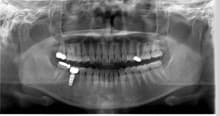

はじめのレントゲンをみると

神経の取ってある向かって左下の奥から2番目の歯(実際は右下奥歯)に

ばい菌感染があり

虫歯も進行し

歯根破折もしていました。

それに伴い

骨の吸収も起こっていました。

治療前のレントゲンです。(実際は左右逆になります。)